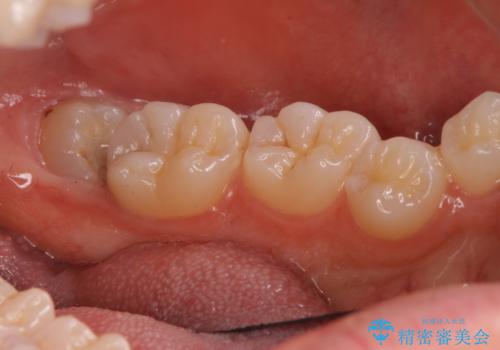

適合の良い詰め物が入りました。

親知らずは虫歯になるリスクが高いため抜歯をする事をお勧めします。